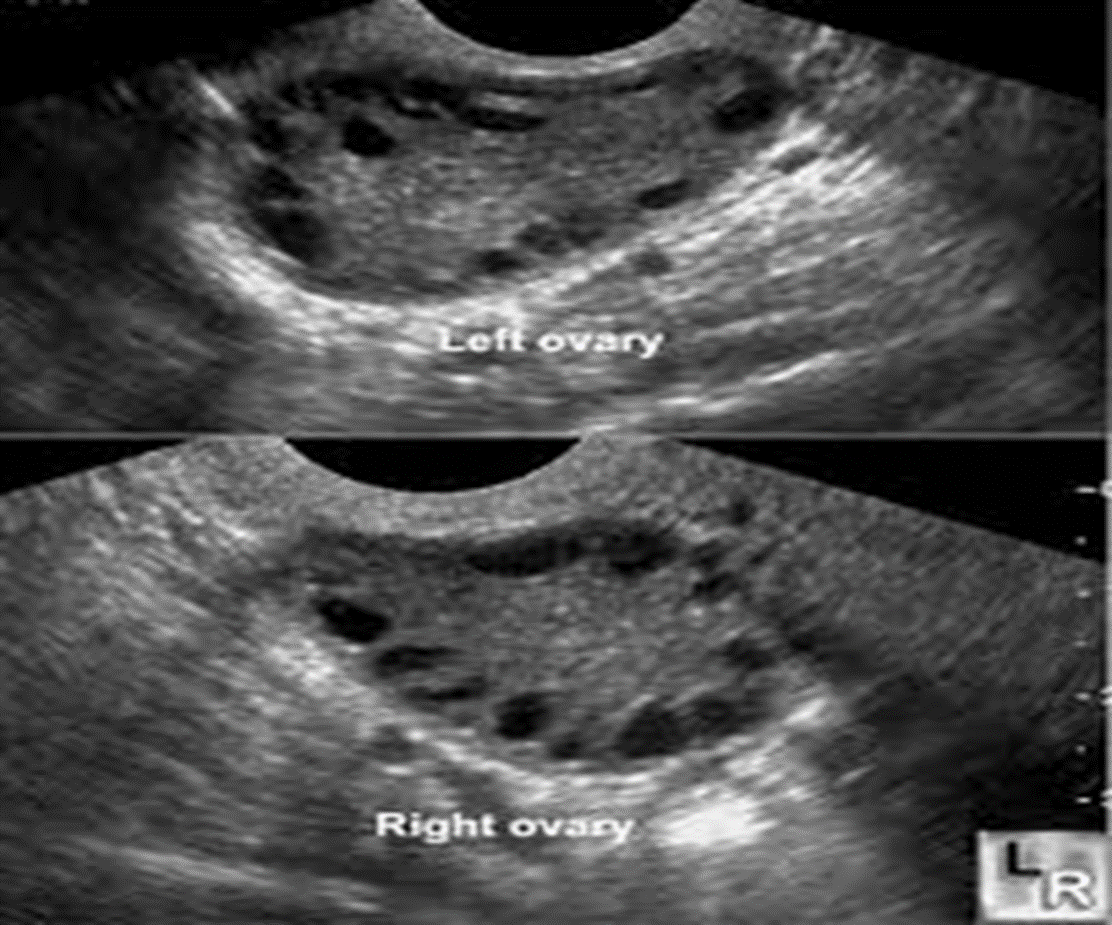

Normal ovary - Ultrasound

- Central echogenic stroma with peripheral anechoic follicles ( 3- 4mm)

- Surrounding hyperechoic Tunica